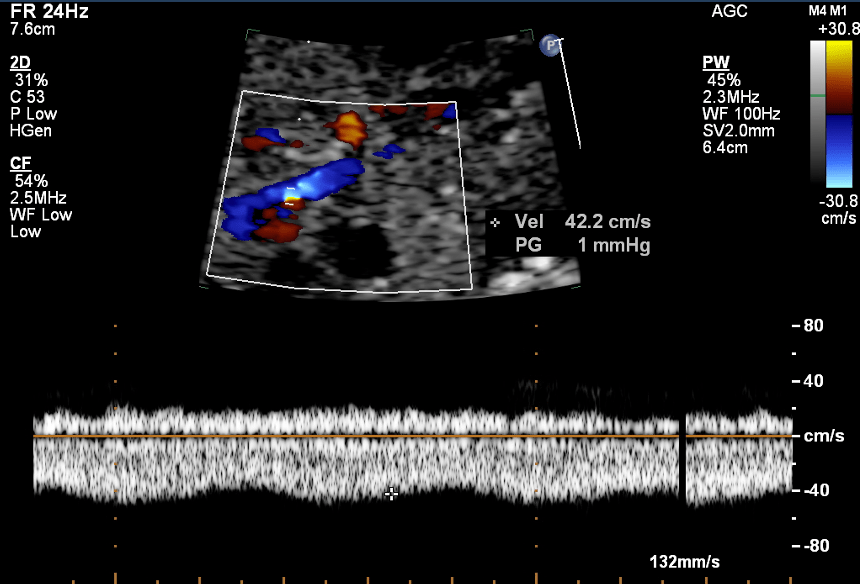

Pulmonary Venous Doppler Patterns

- Doppler waveforms provide critical diagnostic support, and confirmation.

- Biphasic waveforms with reduced pulsatility or abnormal monophasic flow patterns are typical in TAPVC.